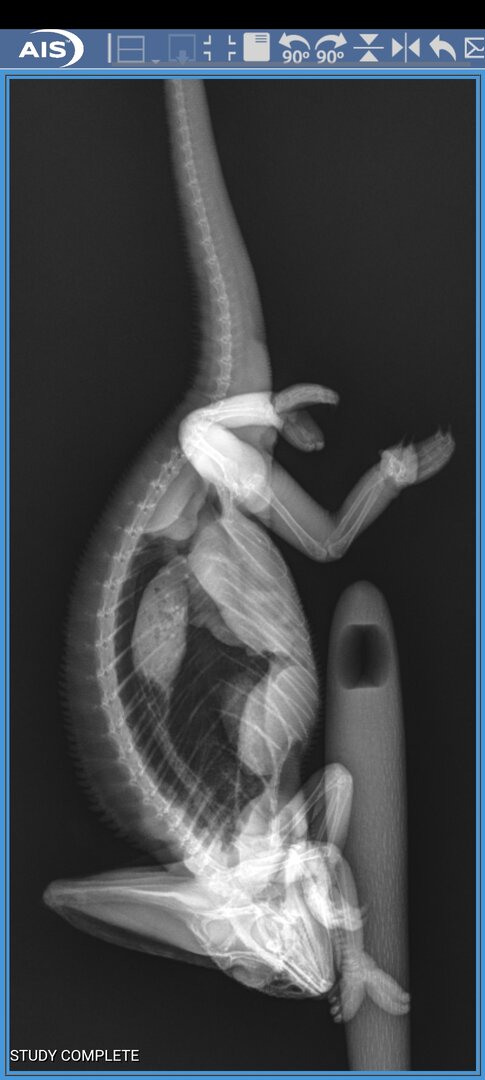

I found an exotic veterinarian that said that she could see him. I brought him in where she did an examination and found that there were no broken bones. However, I saw in the X-ray. What looked to be an impaction. The vet felt that it was not an impaction. I know my little guy and I knew that that was a way too big of a stool to be inside of him. I asked for a dewormer and she also gave me some pain medicine for him and anti inflammatory As well as powdered emergency vet food for him.